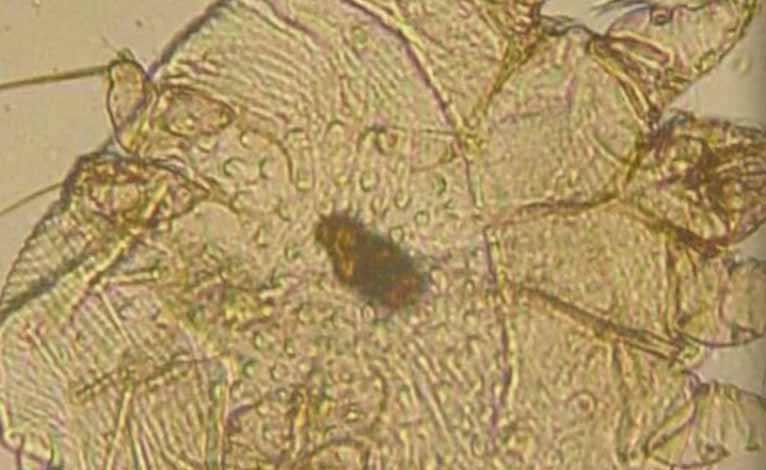

Krätzmilben sind ziemlich klein aber für Menschen mit guten Augen noch ohne Lupe zu erkennen. Besser ist es aber unter einem Vergrößerungsglas die Haut zu untersuchen:

Die Krätzmilben können von unterschiedlicher Farbgebung sein. Von hellbraun über dunkelbraun bis schwarz kann die Milbe unter der Haut erscheinen. Eier und Larven sind heller und eher beige bis gelblich.

Unter die Lupe genommen entstehen Makroaufnahmen wie diese hier von Isotronic-Milbenabwehr. Das Bild zeigt eine Hausstaubmilbe in voller Größe und ähnlich wie bei Grabmilben sieht man deutlich die Beine und den Rüssel. Damit sticht, beisst und gräbt sich die Milbe in und unter die Haut.